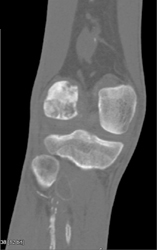

Complex Series of Pelvic Fractures and Diastasis